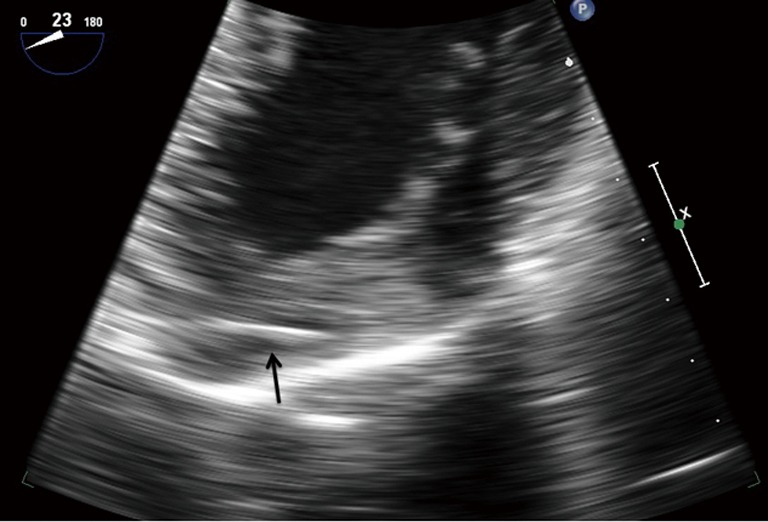

Figure 5.

Intraoperative transesophageal echocardiography showed the second needle (arrow) was in the left ventricular myocardium in mid esophageal four-chamber view.

Based on above findings, left mini-anterolateral thoracotomy was performed with the heart beating. The needle in the chest wall was easily removed from intercostal muscles. However, the second needle in the left ventricular myocardium was invisible from the surface of the heart. A comprehensive TEE examination was performed and the best view to locate the needle from TEE was the mid esophageal four-chamber view. In order to accurately locate the needle, surgeons pressed the tip of the forceps on the probable point of the needle. The tip of the forceps and the needle could be seen on the TEE simultaneously. Then, the needle was removed uneventfully and TEE confirmed that no significant changes in cardiac function after the procedure. Both needles were 4.0 cm in length and 0.25 mm in thickness (Figure 6). Although the whole procedure was on a beating heart, the CPB was kept on standby. No severe bleeding was observed and the operation was successful. The patient was discharged from hospital 5 days after surgery without any complications.